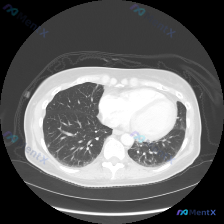

整理了一份胸部CT影像分析资料,和大家一起讨论这个病例。 影像核心异常:双肺弥漫性病变,左肺上叶可见大片融合实变影,密度较高边界模糊,其内可见支气管充气征,实变周围伴磨玻璃密度影及条索影;右肺可见多发散在斑片状、结节状磨玻璃影及实变影;双肺部分区域可见小叶间隔增厚和细微网格影。 整体是多形性病变,同...